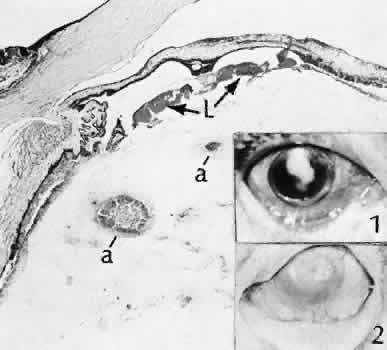

Bacterial inflammation is rare in the delayed period after surgery, except after filtering procedures in which bacteria can gain access to the inside of the eye by way of the bleb (Fig. 48). Another exception to this rule is Priopionibacterium acnes or Staphylococcus epidermidis endophthalmitis, which infects lens remnants and may not clinically manifest for many months after cataract extraction. Fungal endophthalmitis (Fig. 49) may take the form of keratitis or endophthalmitis. Histologic characteristics of end-stage endophthalmitis include fibrovascular organization centered about a chronic nongranulomatous inflammatory reaction contiguous with lens remnants, causing cyclitic membrane formation and retinal detachment.

Fig. 49. Two cases of fungal endophthalmitis following cataract extraction. This is a case of extracapsular cataract extraction in which phacoemulsification was not used. The eye became inflamed 2 months after the procedure and was enucleated 2 weeks later. Multiple fungal abscesses (a) are present in the anterior vitreous. Inset 1 is characteristic of the presentation of fungal endophthalmitis with a well-defined anterior chamber infiltrate associated with minimal signs of inflammation. Inset 2 is illustrative of advanced tissue destruction associated with the inflammatory reaction to fungal organisms.